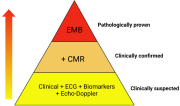

| 06:08, 31 באוקטובר 2023 | Myocarditis3.jpg (קובץ) |  |

130 קילו־בייטים | Motyk | 1 | |

| 14:51, 30 באוקטובר 2023 | Myocarditis2.png (קובץ) |  |

64 קילו־בייטים | Motyk | 1 | |

| 13:08, 30 באוקטובר 2023 | Myocarditis1.png (קובץ) |  |

235 קילו־בייטים | Motyk | 1 | |

| 12:06, 30 באוקטובר 2023 | Myocarditis4.jpg (קובץ) |  |

142 קילו־בייטים | Motyk | 1 | |